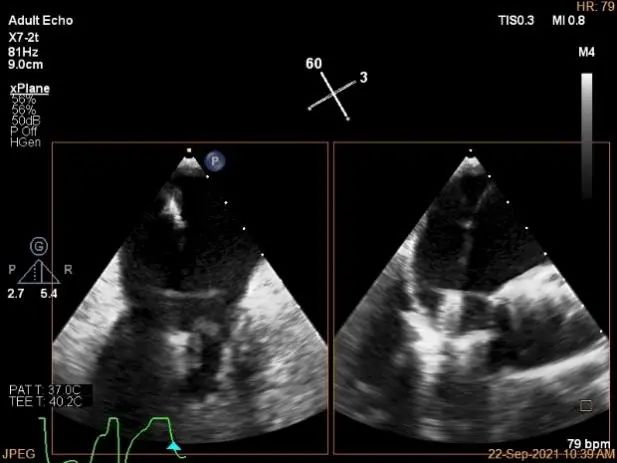

术中超声

房间隔穿刺点选择

穿刺高度:4.3cm

穿刺高度:4.08cm